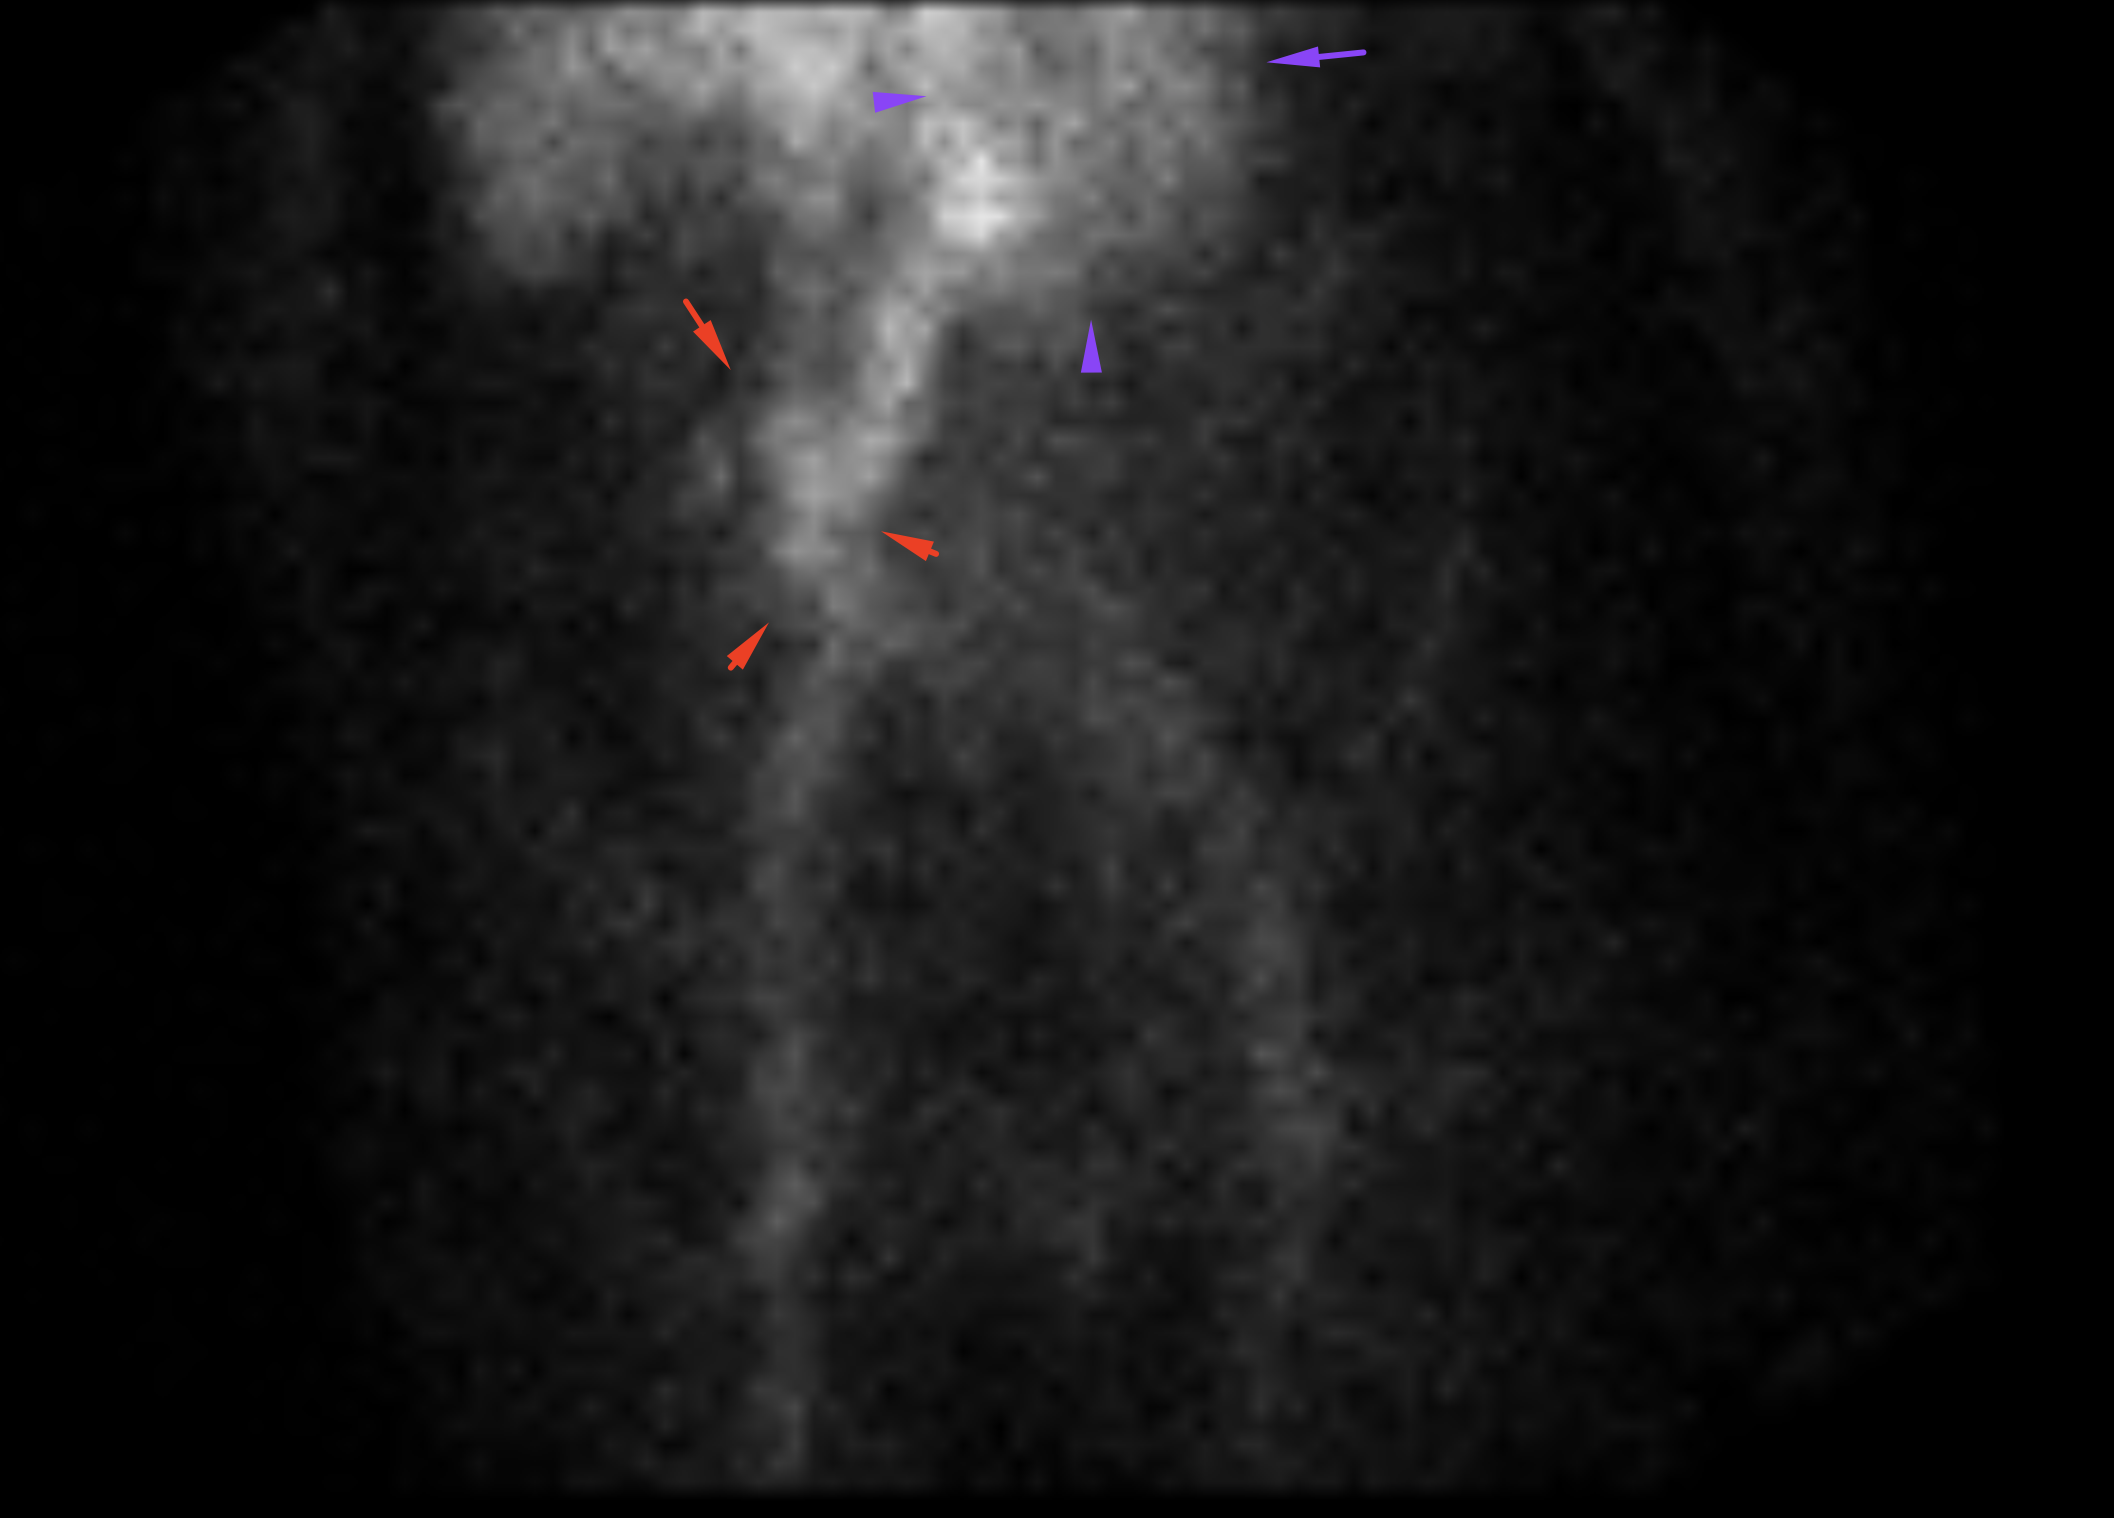

Age: 79

Sex: Female

Indication: Melena

Radiotracer: Tc99m Labeled RBCs

Sample ReportPositive study for active GI bleeding with the origin favored to be in the small bowel.